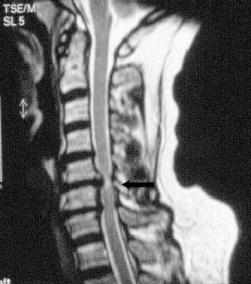

Das Gleiche gilt für Blasen-Mastdarmstörungen und Gangstörungen. Hier kann es aufgrund eines Drucks auf das Rückenmark zu bleibenden Schäden kommen. Dieses Krankheitsbild wird auch als Myelopathie beschrieben.

Durch die Untersuchung und Anamneseerhebung ergeben sich wichtige Hinweise auf die Ursachen der Beschwerden. Hieran orientiert sich auch maßgeblich die Empfehlung für oder gegen eine Operation. Ergänzend sind häufig konventionelle Röntgenaufnahmen sowie eine Kernspintomographie sinnvoll. Knochenveränderungen werden besser mit der Computertomographie erfasst. Besteht der Verdacht auf eine Rückenmarkserkrankung oder eine Störung der Nervenfunktion wird eine elektrophysiologische Untersuchung (evozierte Potentiale) organisiert. Hierbei wird, ähnlich wie bei einem Stromkabel, die Durchgängigkeit der Nervenbahnen gemessen.

Versteifung der Halswirbelsäule von ´hinten´:

Bei einer lang gestreckten Verengungen des Rückenkanals muss das Rückenmark wieder genügend Platz bekommen. Dies gelingt in seltenen Fällen nur durch eine knöcherne Öffnung des Spinalkanals von hinten. Dazu ist eine Versteifung der Wirbel mit einem Schrauben-/Stangensystem erforderlich. Das ist in diesen Fällen die einzige Möglichkeit um einer Zunahme eines Rückenmarksschadens mit Querschnittssymptomen vorzubeugen. Diese Operation führe ich in Diez gemeinsam mit Prof. Schönmayr durch.